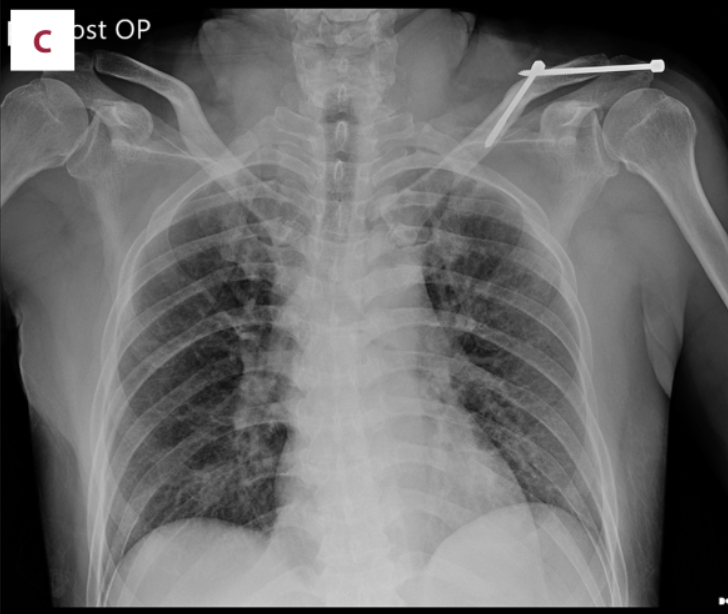

植入物取出后,胸片显示锁骨骨折完全愈合,随访1年,肩锁关节脱位保持良好复位